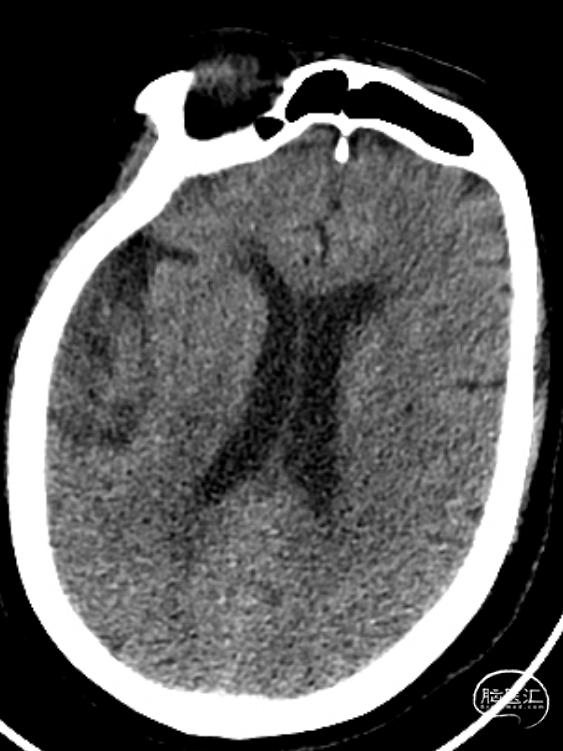

术前检查

患者为急性脑梗死,头颅CT未见明显低密度病灶,CTA提示:右侧颈内动脉及右侧大脑中动脉M1段闭塞,远端分支减少,显影浅淡。目前患者神经功能缺损严重,有急诊取栓手术指征。

术后第一天复查颅脑CT未见异常染色及大面低密度病灶。

查头颅MRI:右侧基底节区、右侧顶颞岛叶急性脑梗死。